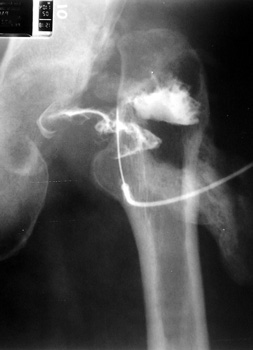

Arthrographic evidence of looseningcontrast enters

abnormally widened interface Gruen zone 1 and 2

Arthrographic evidence of cup looseningcontrast enters

abnormally widened interface Gruen zone II and III